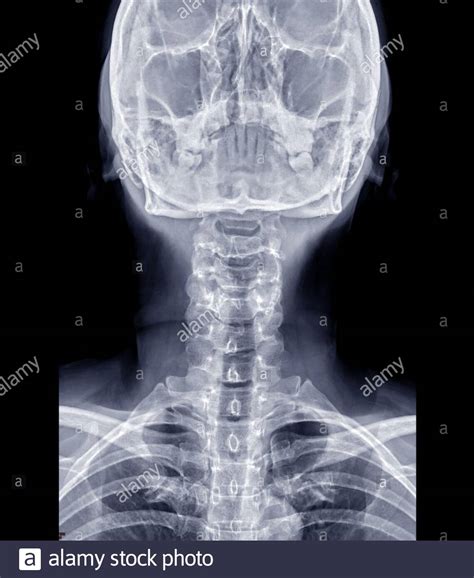

A cervical spine X-ray is a non-invasive diagnostic test that uses electromagnetic radiation to create images of the seven vertebrae located in the neck. These vertebrae, labeled C1 through C7, support the weight of the skull and facilitate head movement. When a radiologist or physician reviews these images, they are looking for specific markers of skeletal integrity.

• Proper Alignment: The vertebrae should form a smooth, gentle curve known as the lordotic curve. A "straightened" spine, often caused by muscle spasms, can indicate an underlying issue.

• Bone Integrity: The vertebrae should show no signs of fractures, chips, or abnormal bone loss.

• Joint Space: The spaces between the vertebrae (where the discs reside) should be uniform. While X-rays cannot show discs directly, a narrowing of the space can suggest disc degeneration.

• No Foreign Bodies or Lesions: There should be no abnormal growths, tumors, or metallic fragments visible in the soft tissue or bone structure.